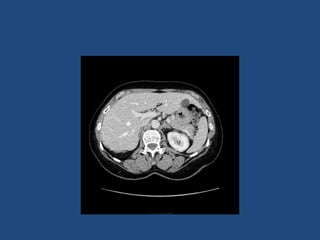

Imaging

• CT better at eliminating malignancy

(dedicated CT looking at Hounsfield units (HU)

and washout characteristics)

– <10HU = benign (sens 71%, spec 100%)

• MRI may characterise phaeos better

• FDG-PET good for phaeos and cancer

• FNA – consider if cancer history and >10HU on CT

after exclusion of phaeo

Imaging - size

• >4cm 90% sensitivity carcinomas

24% specificity (ie only 24% cancer)

• >6cm 25% chance of it being carcinoma

• <2cm + hypodense then unlikely to grow

• If change in size >1cm over 6 months consider

resection

Practical suggestion

• Most have not had dedicated CT (ie bottom of CT

chest or CT colon)

• If <4cm do dedicated adrenal CT 6 months after

presentation

– No need to rescan if no change in size (or <0.8cm)

• If >4cm do dedicated adrenal CT when referred to

get characteristics and consider repeat or MRI in a

further 6 months if looks benign

• <2cm and no change then discharge

2- 4cm monitor clinically for longer?

Imaging • CT betterat eliminating malignancy (dedicated CT looking at Hounsfield units (HU) and washout characteristics) – <10HU = benign (sens 71%, spec 100%) • MRI may characterise phaeos better • FDG-PET good for phaeos and cancer • FNA – consider if cancer history and >10HU on CT after exclusion of phaeo

Imaging - size •>4cm 90% sensitivity carcinomas 24% specificity (ie only 24% cancer) • >6cm 25% chance of it being carcinoma • <2cm + hypodense then unlikely to grow • If change in size >1cm over 6 months consider resection • Guidelines suggest: – NIH: 2 CTs 6M apart – Young et al + UptoDate: 0,6,12,24m – BES: Repeat image – increase in size of 0.8cm over 6-12M consider surgery

Practical suggestion • Mosthave not had dedicated CT (ie bottom of CT chest or CT colon) • If <4cm do dedicated adrenal CT 6 months after presentation – No need to rescan if no change in size (or <0.8cm) • If >4cm do dedicated adrenal CT when referred to get characteristics and consider repeat or MRI in a further 6 months if looks benign • <2cm and no change then discharge 2- 4cm monitor clinically for longer?